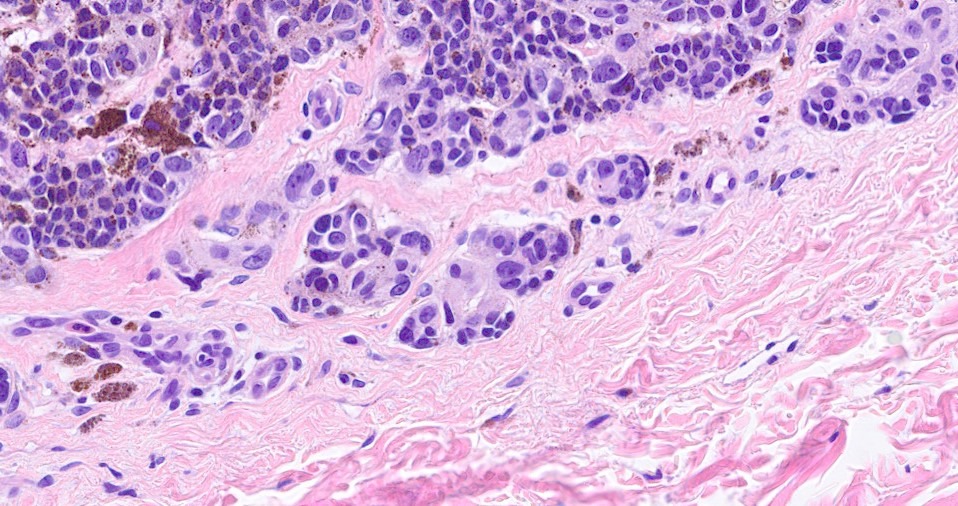

•Large dyscohesive nests with retraction artifact, not restricted to the tips of the epidermal ridges

•Heavy pigmentation (sometimes gray/green)

•Variable atypia (can be marked)

•Superficial dermal atypia

•Junctional mitoses sometimes present, dermal mitoses+/-, can be multiple but never atypical